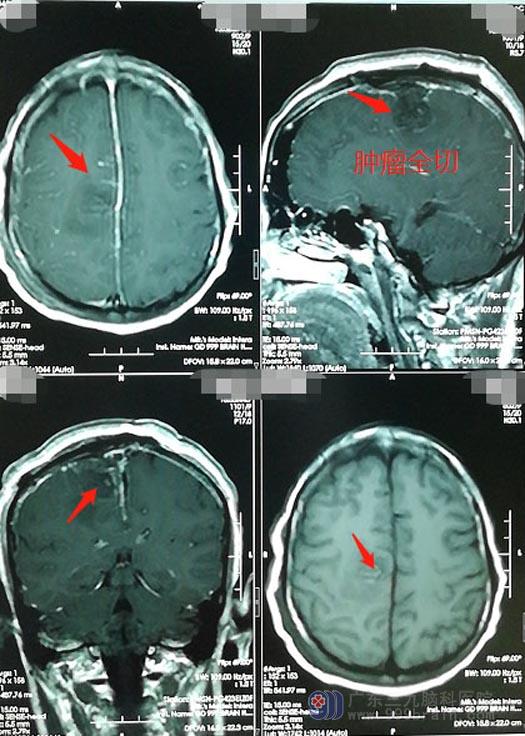

覃阿姨的肿瘤位于中央沟处并突入上矢状窦内,属于脑功能区,手术稍有不慎很有可能导致患者对侧偏瘫。医院副院长、神经外五科主任鲁明带领团队制定了详细的手术方案并主刀手术。术中发现肿瘤已经侵犯长入上矢状窦内,与周围正常脑组织粘连紧密;术中切开静脉窦,将窦内的肿瘤一并彻底切除;再将静脉窦修补,静脉窦属于颅内大的引流静脉,血流丰富,修补过程既要考虑血管重建通畅情况又要避免出血较多及空气栓塞风险。最终,肿瘤被彻底切除,极大地避免了再复发的风险。这样的操作需要足够的技术与担当,只有对自身手术技术非常自信才能追求彻底的切除,否则可能会出现两种结果,要么损伤脑组织导致患者偏瘫,要么肿瘤残余遗留隐患。

术后病理检查结果:纤维性脑膜瘤(WHOI级),属于良性,考虑肿瘤突入静脉窦,术中虽然彻底切除,但仍建议患者待恢复平稳后再进一步放疗,巩固治疗并最大可能地避免肿瘤复发。